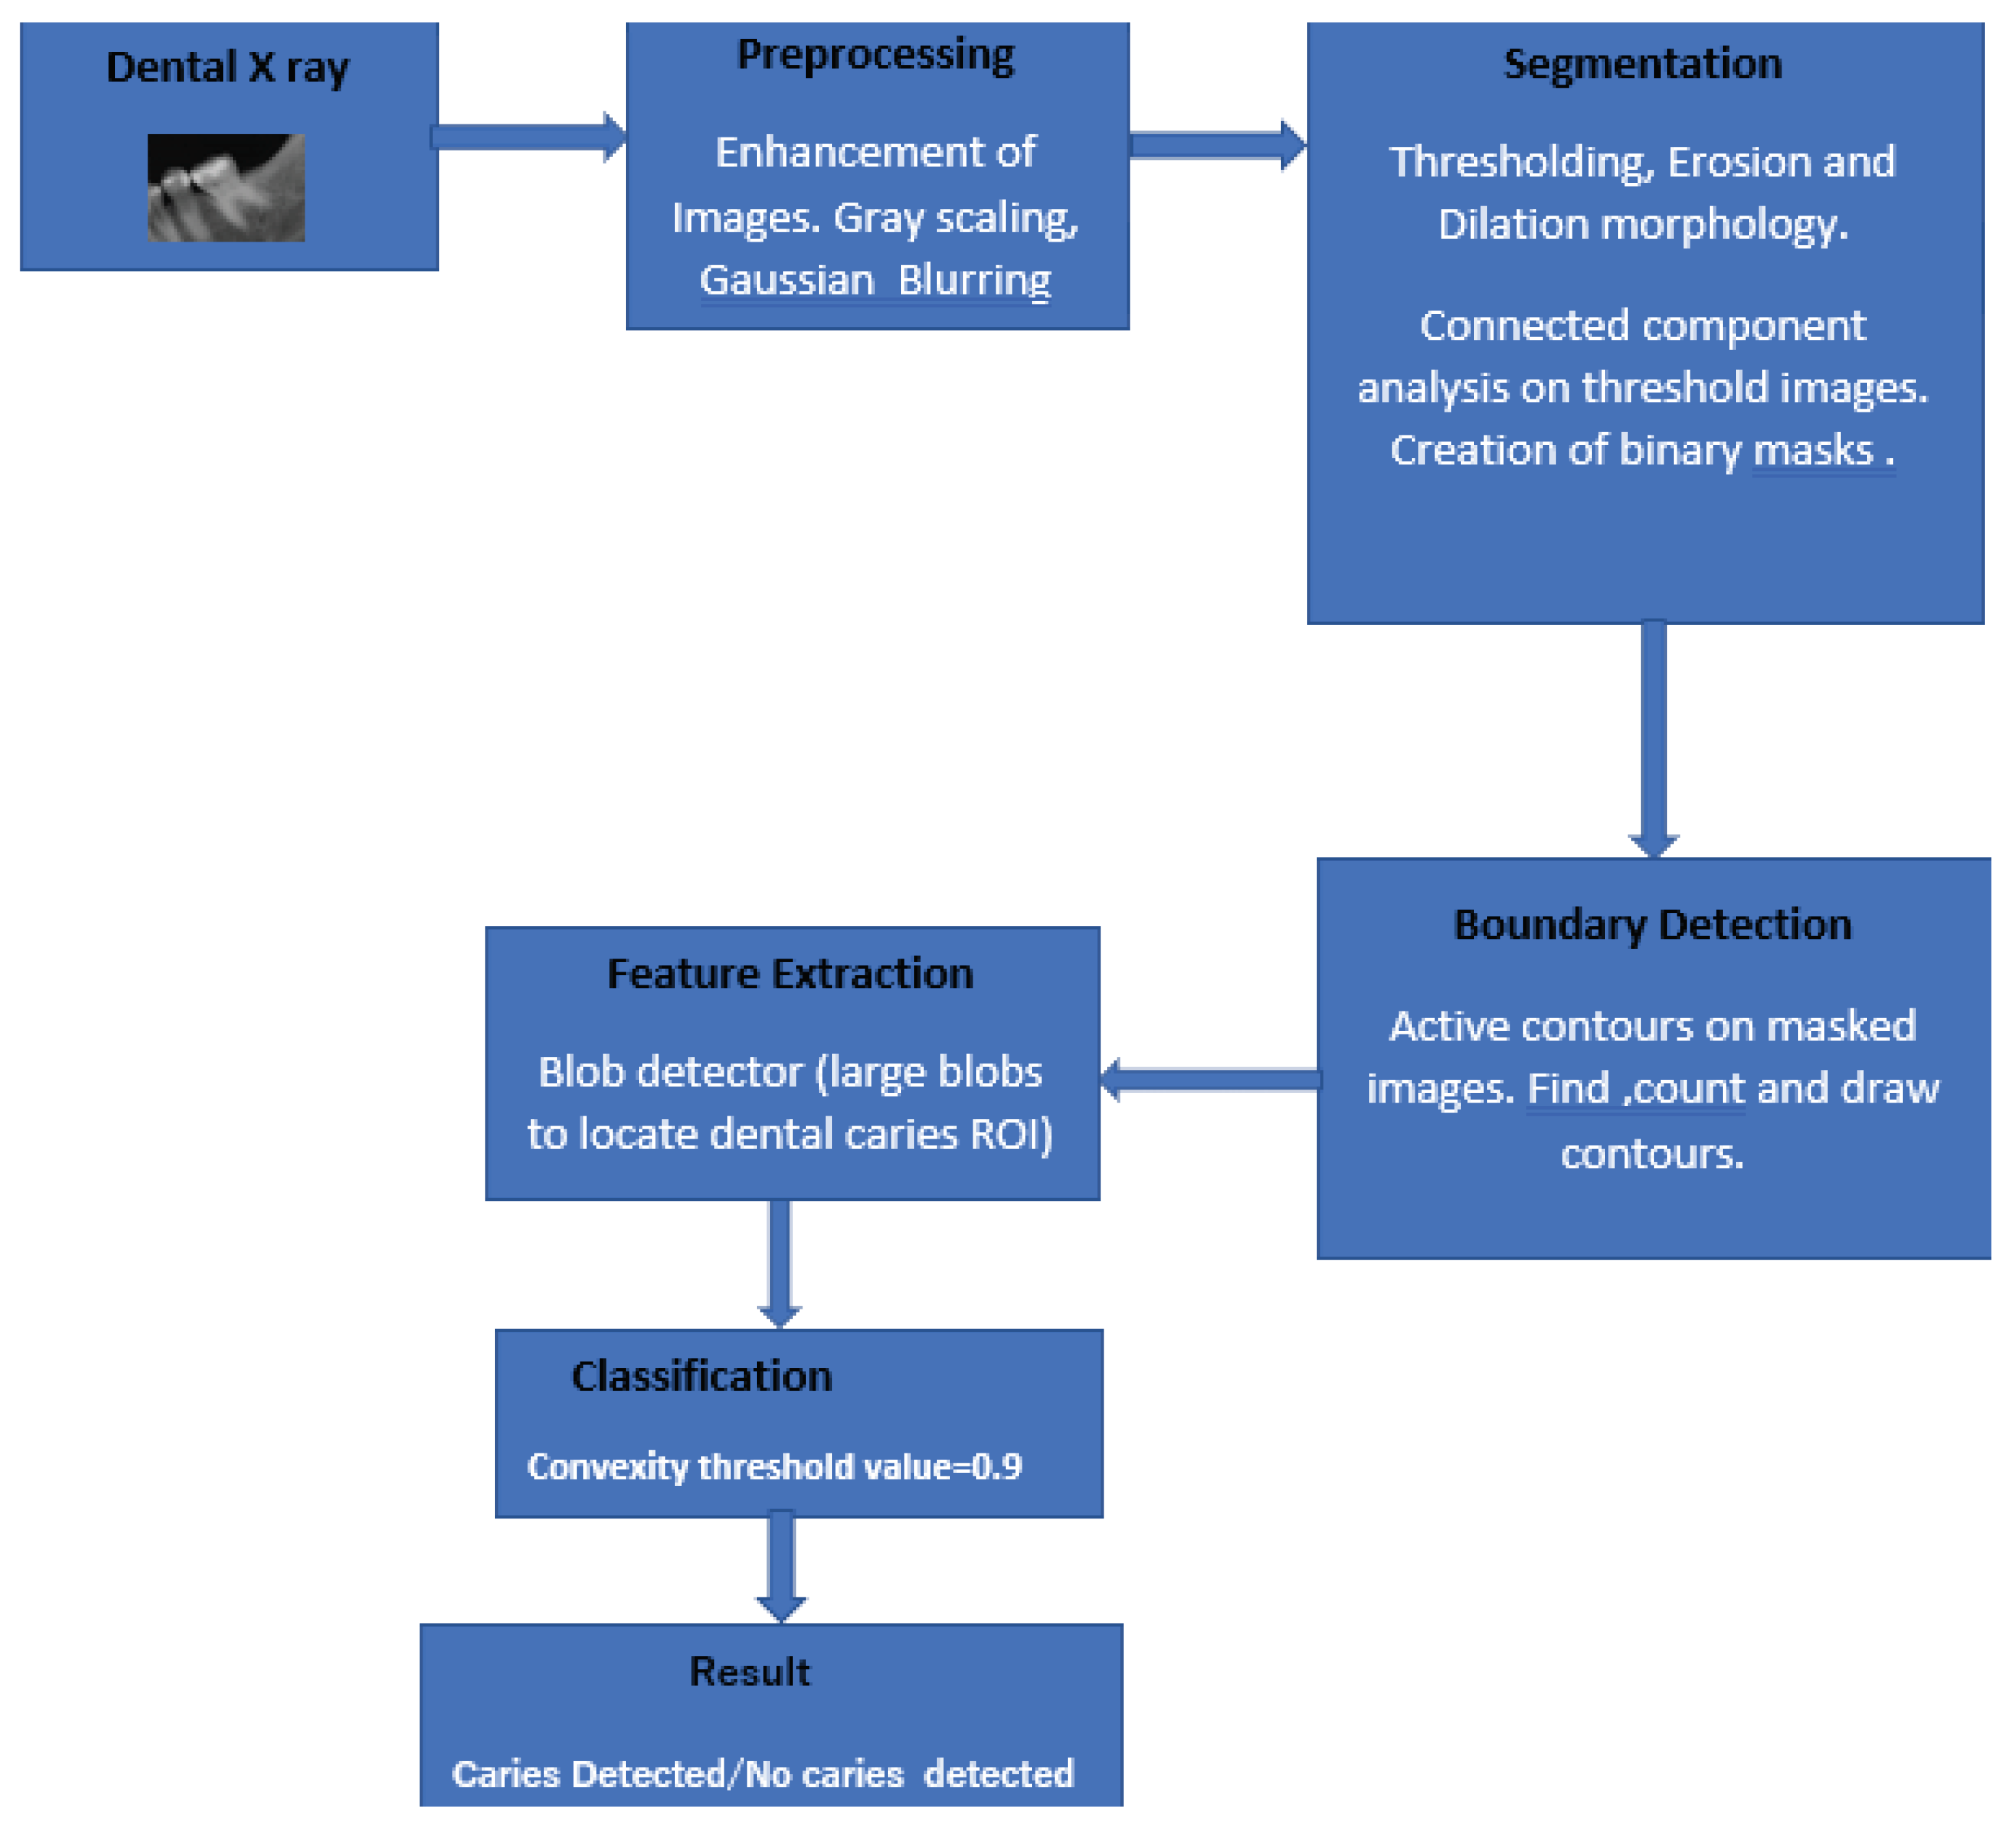

2. Methods and Techniques

2.1. Pre-Processing of Dental Images

2.2. Segmentation of Images

2.3. Feature Extraction

2.3.1. Noise Reduction

2.3.2. Caries Candidate Detection

2.3.3. Caries Candidate Selection